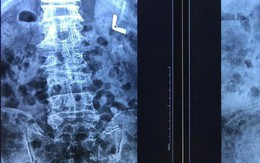

Sống khỏe 2018-10-11T19:35:00Bệnh viện đa khoa Đức Giang (Hà Nội) vừa tiếp nhận điều trị cho cụ ông 72 tuổi bị biến dạng cột sống.

Giải trí 2025-11-25T23:15:00Lê Giang cho biết nhiều tháng qua cô xuất hiện nhiều cơn đau đến mức không thể đi nổi, có lúc phải lết vào nhà tắm khóc vì thoát vị đĩa đệm chèn thần kinh tọa. Cơn đau kéo dài khiến chân nữ nghệ sĩ yếu dần, xuất hiện dấu hiệu teo cơ.